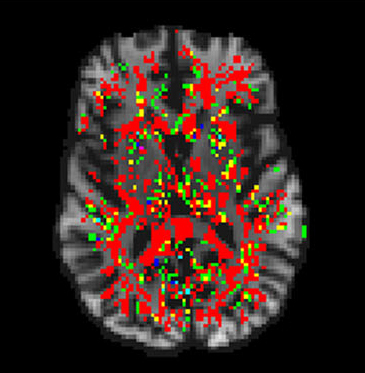

Para lograr ese objetivo, los investigadores hicieron una selección aleatoria de puntos del cerebro sobre los que debería concentrarse el resonador para captar información. “Es como si, para hacer un buen mapa de una ciudad, no fuera necesario describir toda su superficie sino sólo un porcentaje de cuadras”, explicó a la Agencia CyTA-Leloir el doctor Nicolás Lori, del Instituto de Neurociencia Cognitiva y Traslacional (INCYT), que tiene sede en Rosario y depende de la Fundación INECO, de la Universidad Favaloro y del CONICET.

Los puntos elegidos se establecen, explicó Lori, dividiendo la imagen del cerebro en cubos y ubicándolos en el centro de cada uno de ellos. “En la actualidad, el procesamiento de datos, aunque es muy variable, puede tomar muchas horas. Y eso se vuelve exponencial cuando deben estudiarse muchos pacientes y realizarse muchos análisis diferentes en cada caso. Nuestra tecnología de software logra los mismos resultados en la mitad del tiempo requerido”, indicó el doctor en física ydirector de Laboratorio de Neuroimágenes y Neurociencias (LANEN) en el INCYT. El trabajo fue publicado en la revista “Journal of Medical Systems”.

El método liderado por investigadores del Instituto de Neurociencia Cognitiva y Traslacional reduce a la mitad el tiempo de procesamiento de imágenes del cerebro obtenidas con resonancia magnética.